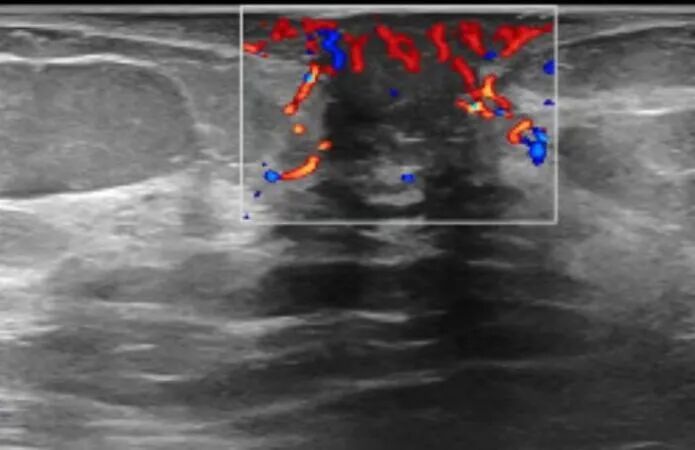

超声描述:左乳乳晕区可见一大小21.5x5.x9.5mm的低回声区,形态不规则,平行位,边缘不光整,内部回声不均匀,可见导管样回声及点状强回声。 CDFI 示该团块内血供不丰富。

超声诊断:左乳乳晕区低回声区(非肿块型占位可能), BI - RADS IVA ,建议穿刺活检。